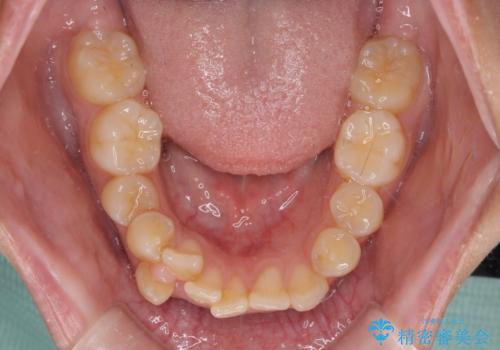

- 八重歯と、上下前歯が接触しないくらい前突した前歯を気にして来院された患者様です。

奥歯の噛み合わせは正常に近い状態でしたが、右上の奥歯に突起があったり、上下前歯が非接触であったりしていたため、補助装置を使用して上顎前歯を積極的に引っ込めるように計画しました。

口元の突出感を改善するために上下左右の小臼歯4本を抜歯し、ワイヤー装置によりデコボコを解消しながら口元の突出感も改善していくこととしました。